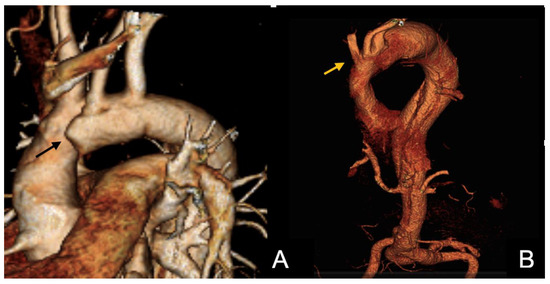

Reverse-Wire TEVAR for Subacute Type B Aortic Dissection with Severe True-Lumen Collapse: A Case Report

Type B aortic dissection (TBAD) requires management tailored to the disease phase and clinical presentation, with the subacute period representing a favorable window for endovascular intervention due to improved procedural safety and remodeling potential. We report the case of a 38-year-old male with [...] Read more.

Type B aortic dissection (TBAD) requires management tailored to the disease phase and clinical presentation, with the subacute period representing a favorable window for endovascular intervention due to improved procedural safety and remodeling potential. We report the case of a 38-year-old male with hypertension, dyslipidemia, and bicuspid aortic valve disease who presented one month after symptom onset with persistent chest pain and progressive bilateral lower-limb numbness. Clinical examination suggested early spinal cord ischemia, while laboratory tests demonstrated acute hepatic and renal dysfunction. CT angiography revealed a subacute TBAD with a markedly expanded false lumen and near-complete compression of the true lumen, resulting in visceral, renal, and potential spinal malperfusion. Given the high-risk anatomy and evolving organ dysfunction, a staged hybrid strategy was undertaken. A left carotid–subclavian bypass was performed to secure proximal landing for endovascular repair, followed the next day by thoracic endovascular aortic repair (TEVAR) using two thoracic stent grafts. Postoperative recovery was favorable, with rapid resolution of neurological symptoms and normalization of hepatic and renal parameters, allowing discharge on postoperative day seven. This case underscores the importance of early recognition of malperfusion and timely hybrid intervention in subacute TBAD with severely compressed true lumen, demonstrating excellent early clinical outcomes. Full article